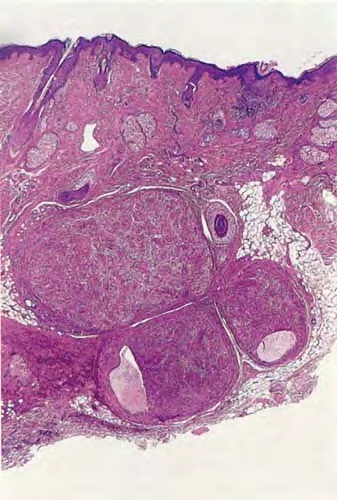

Nodular hidradenoma =الغدوم العرقي العقيدي